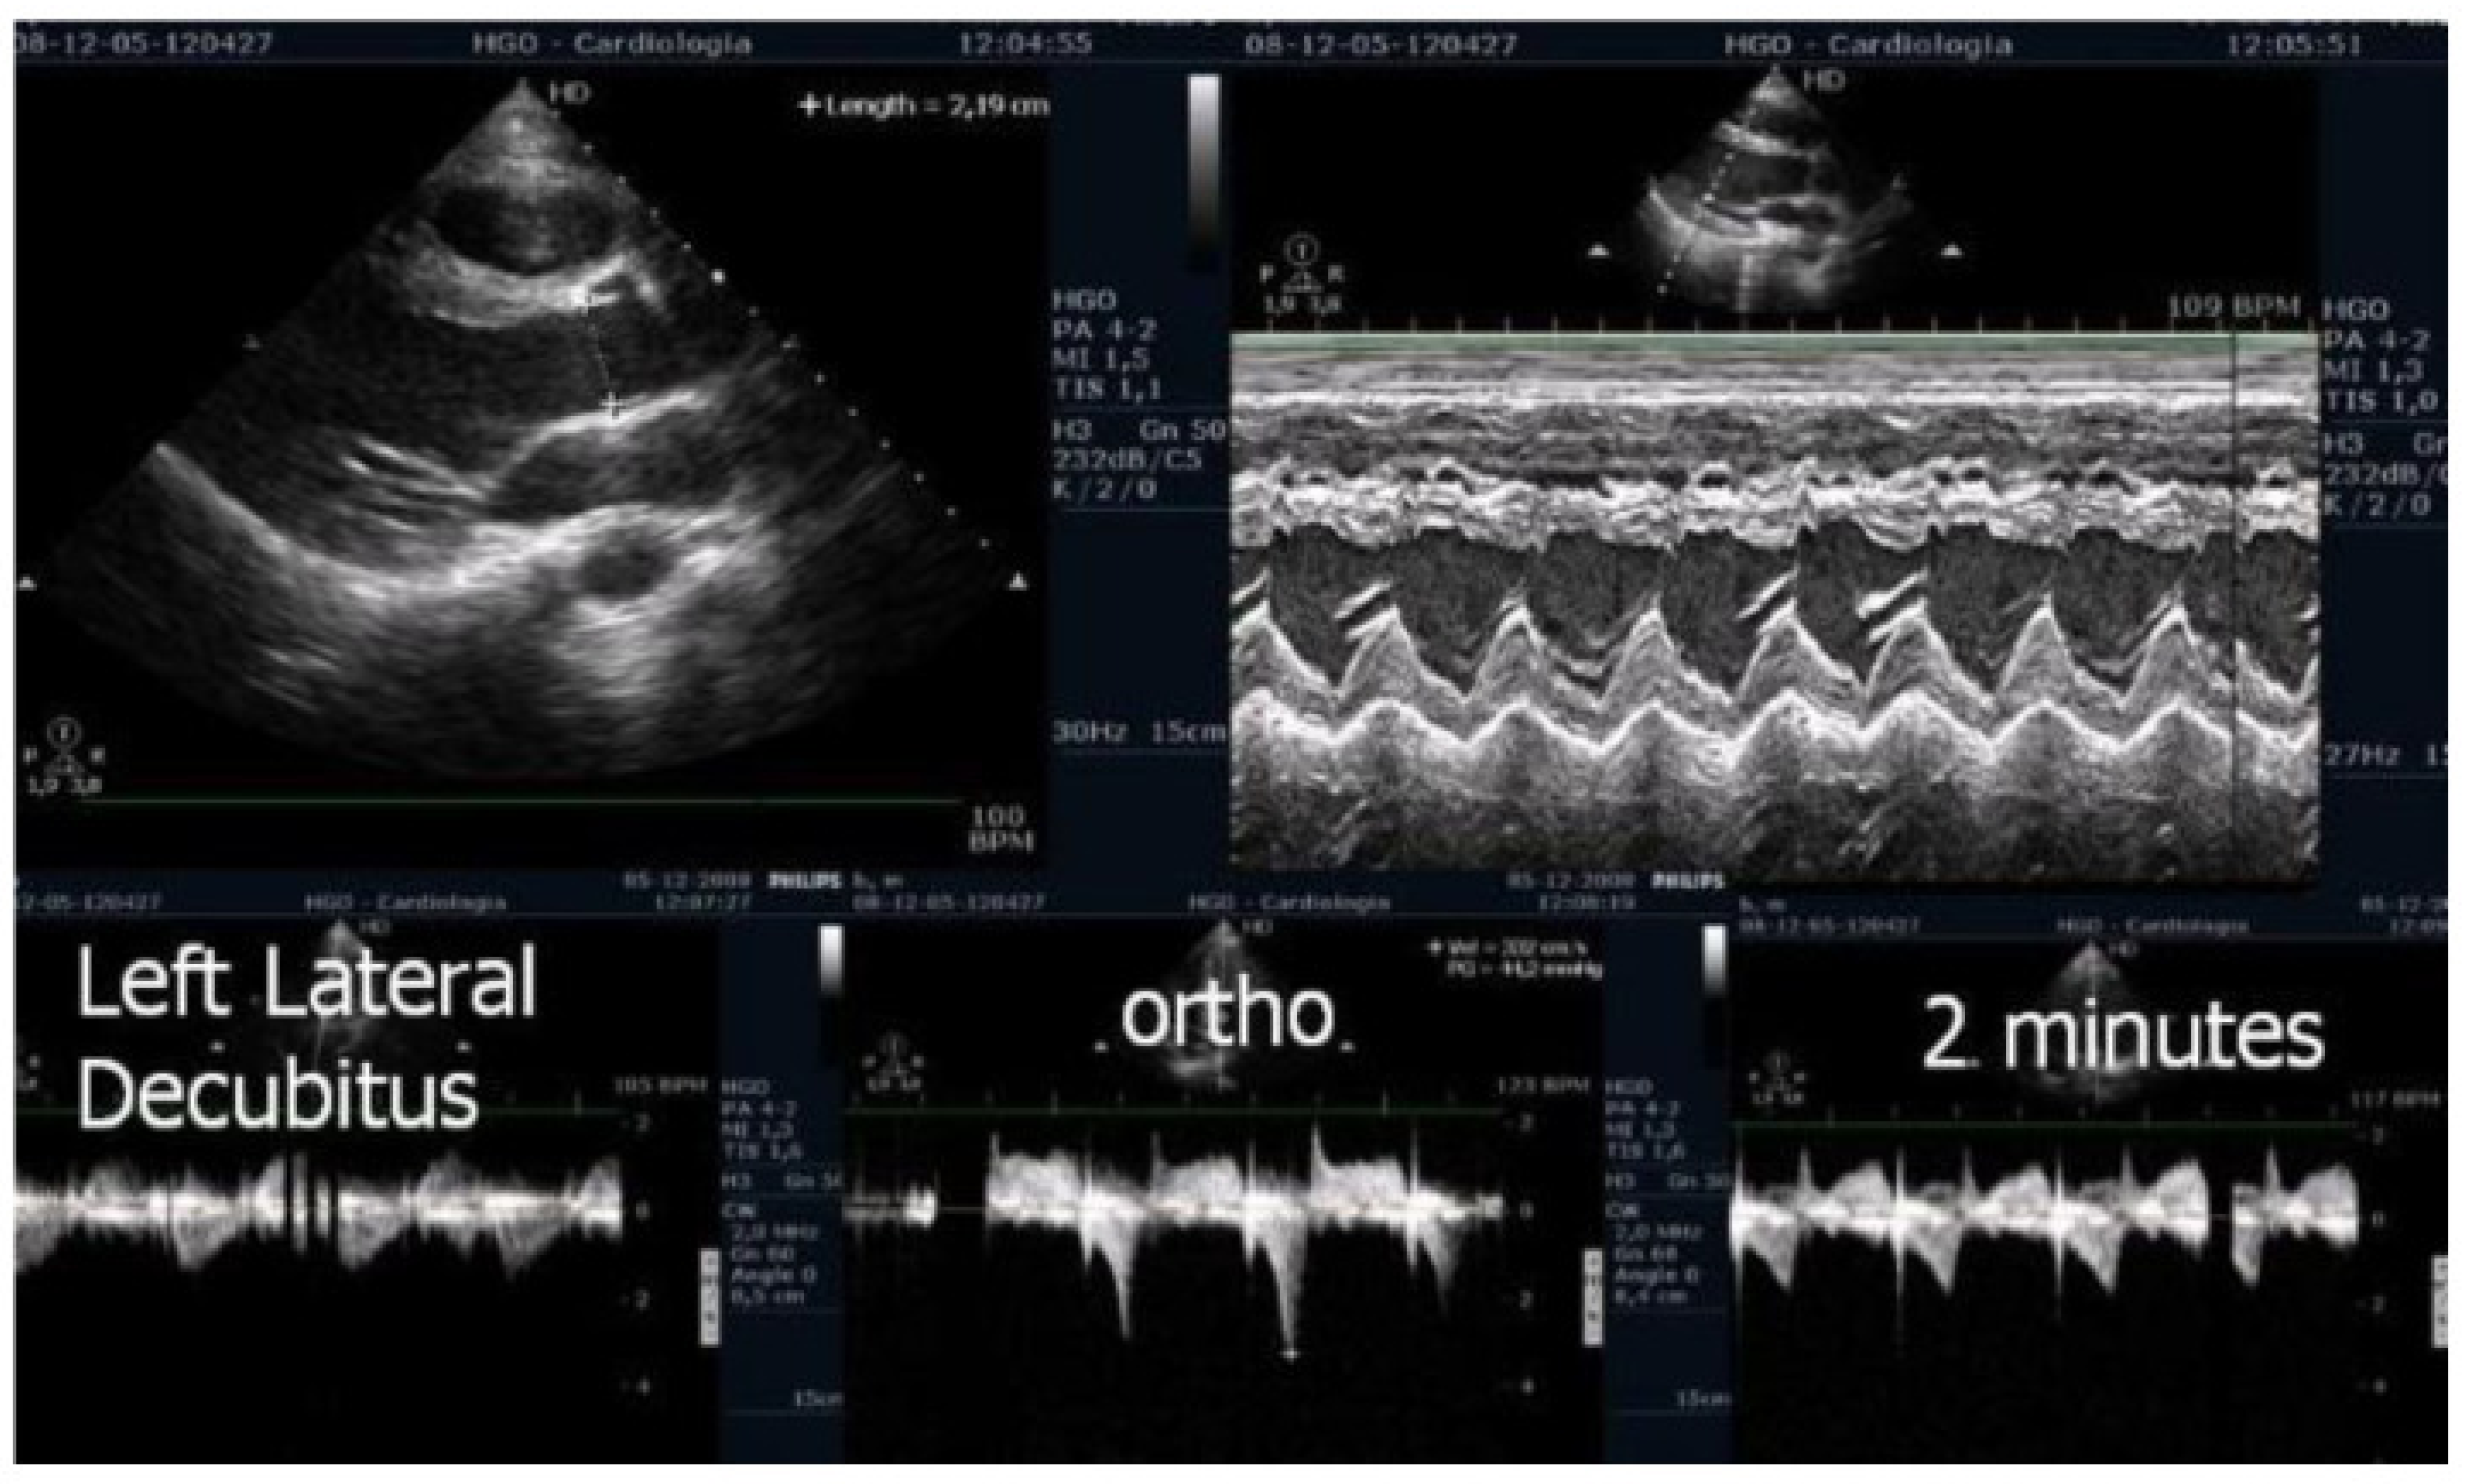

We observed the development of intraventricular pressure gradients (IVPGs) in adolescents without left ventricular hypertrophy upon assumption of an upright posture prior to exercise—a phenomenon previously described in patients with hypertrophic cardiomyopathy [3]. At the onset of exercise (Figure 5), the IVPG initially decreased, likely due to increased preload resulting from activation of the lower limb musculature. However, as exercise progressed, the IVPG steadily increased (Figure 6). After exercise, maintaining an upright posture led to a more pronounced reduction in preload, compared to a supine position. This hemodynamic shift likely accounts for the post-exercise elevation in IVPG observed in most adolescents studied. This postural response may also explain the orthostatic recovery IVPG observed in one highly symptomatic adolescent who presented with exertional angina and ST-segment abnormalities (Figure 7). Additionally, Figure 8 illustrates the impact of beta-blocker therapy on ESE findings in one patient, including the titration of atenolol to a dose of 50 mg, underscoring the clinical relevance of individualized treatment.

Figure 5.

Echocardiography before exercise in a symptomatic adolescent in the left lateral decubitus position, and in the orthostatic position before and at the beginning of exercise [3].

Figure 6.

IVPG at different stages of exercise in the same symptomatic adolescent [3].